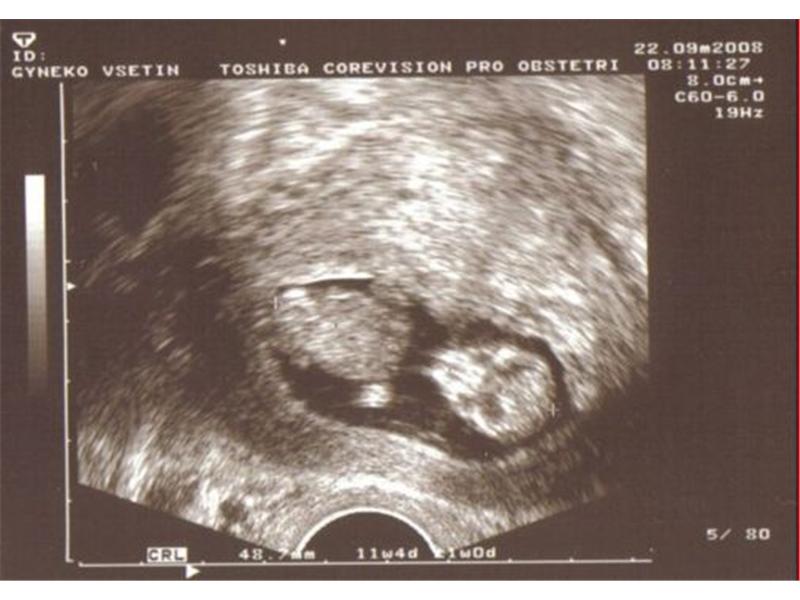

Sono